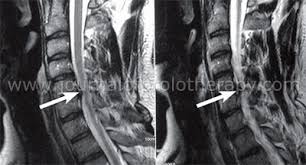

Nerve root pain is variably described as knifelike or aching and is widely distributed projecting to the sclerotome defined as deep structures such as muscles and bones innervated by the root. Lumbar Radiculopathy Nerve Root Compression Lumbar radiculopathy refers to disease involving the lumbar spinal nerve root. The Laser Spine Institute lists sciatica symptoms as pain numbness tingling and burning.

Lumbar radiculopathy is typically caused by a compression of the spinal nerve root. Typically root pain is aggravated by coughing sneezing and straining at stool actions that require a Valsalva maneuver and raise intraspinal pressure. Loss of strength reflex and sensation occurs in the territory of the compressed root. There is a significant volume of literature that would point to the neural tissues themselves as the most logical structures for future research that attempts to interfere with the natural history of this disease from the standpoint of pain. It is defined as sudden usually unilateral severebrief stabbing lancinating recurring pain in the distribution of one or more branches of the Vth cranial nerve Trigeminal neuralgia also known as prosopalgia or fothergills disease is aneuropathic disorder characterized by episodes of intense pain in the face originating from trigeminal nerve. Herniated disc causing a single nerve root compression leg pain back pain. An estimated 20 million Americans suffer from peripheral nerve damage aka.